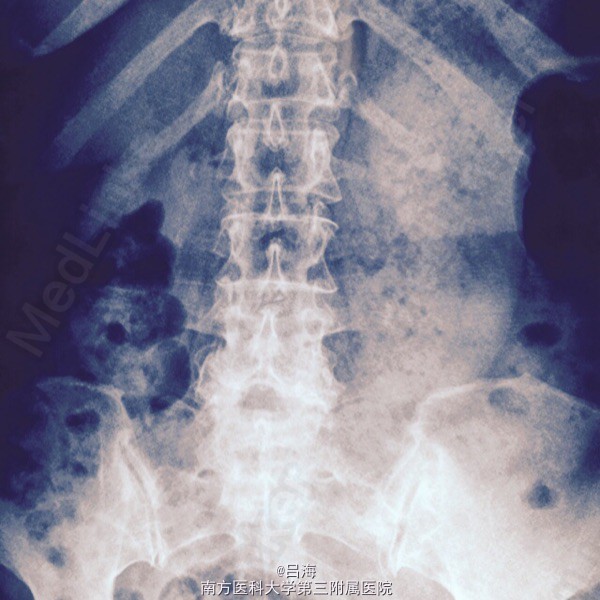

腰痛伴双下肢麻痛无力3年,加重1周。腰椎活动受限,弯腰时明显,间歇性跛行。

下腰压痛,并向双下肢放射,直腿抬高试验阴性。 腰椎DR,CT提示:腰5椎体二度滑脱并峡部裂,椎管狭窄

腰5椎体II度滑脱并峡部裂;椎管狭窄症。 后路腰5全椎板切除减压,滑脱复位,椎间cage植骨融合,经椎弓根内固定术